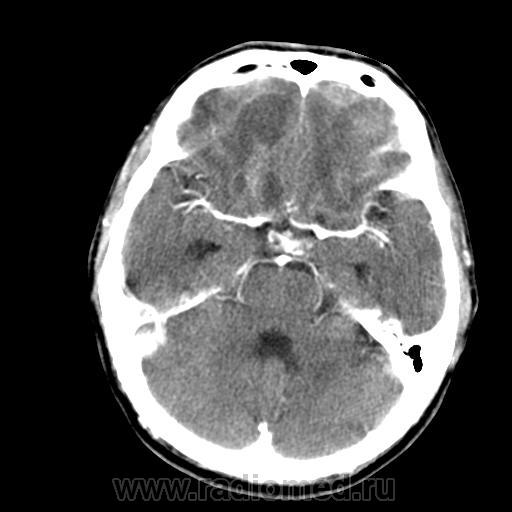

3-я - в этот же день с контрастным усилением (артер. фаза).